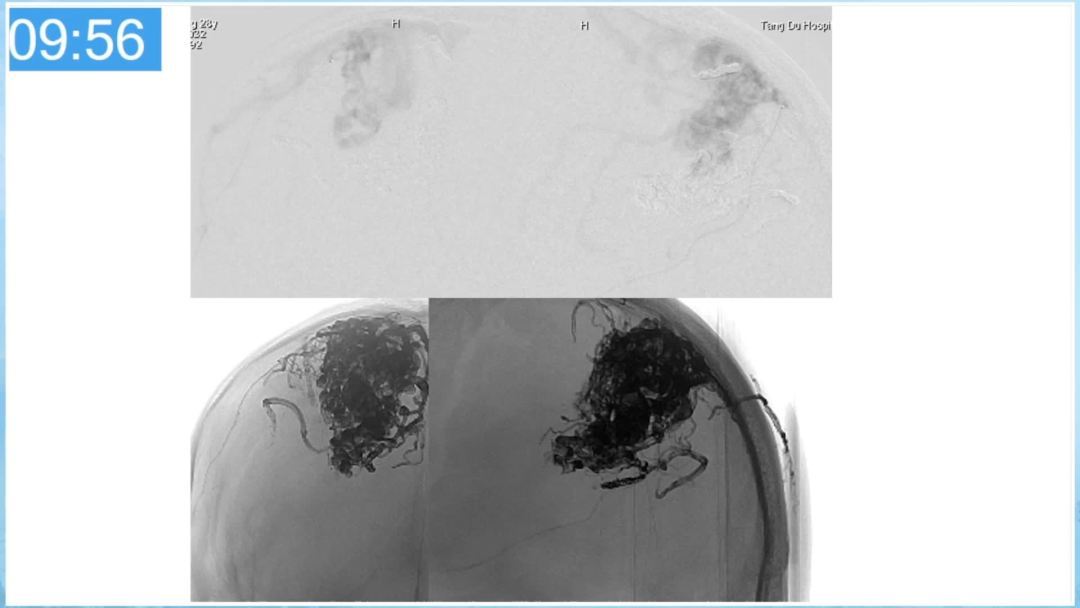

本期为大家特别分享:空军军医大学唐都医院邓剑平教授的精彩会议内容《颅内动静脉畸形的复合手术治疗》,欢迎大家阅读和分享!

合理的复合平台下的综合治疗,针对每一个病变对应不同方法安全性分析,不预设、不排斥,每种技术发挥到最佳,互相保障。